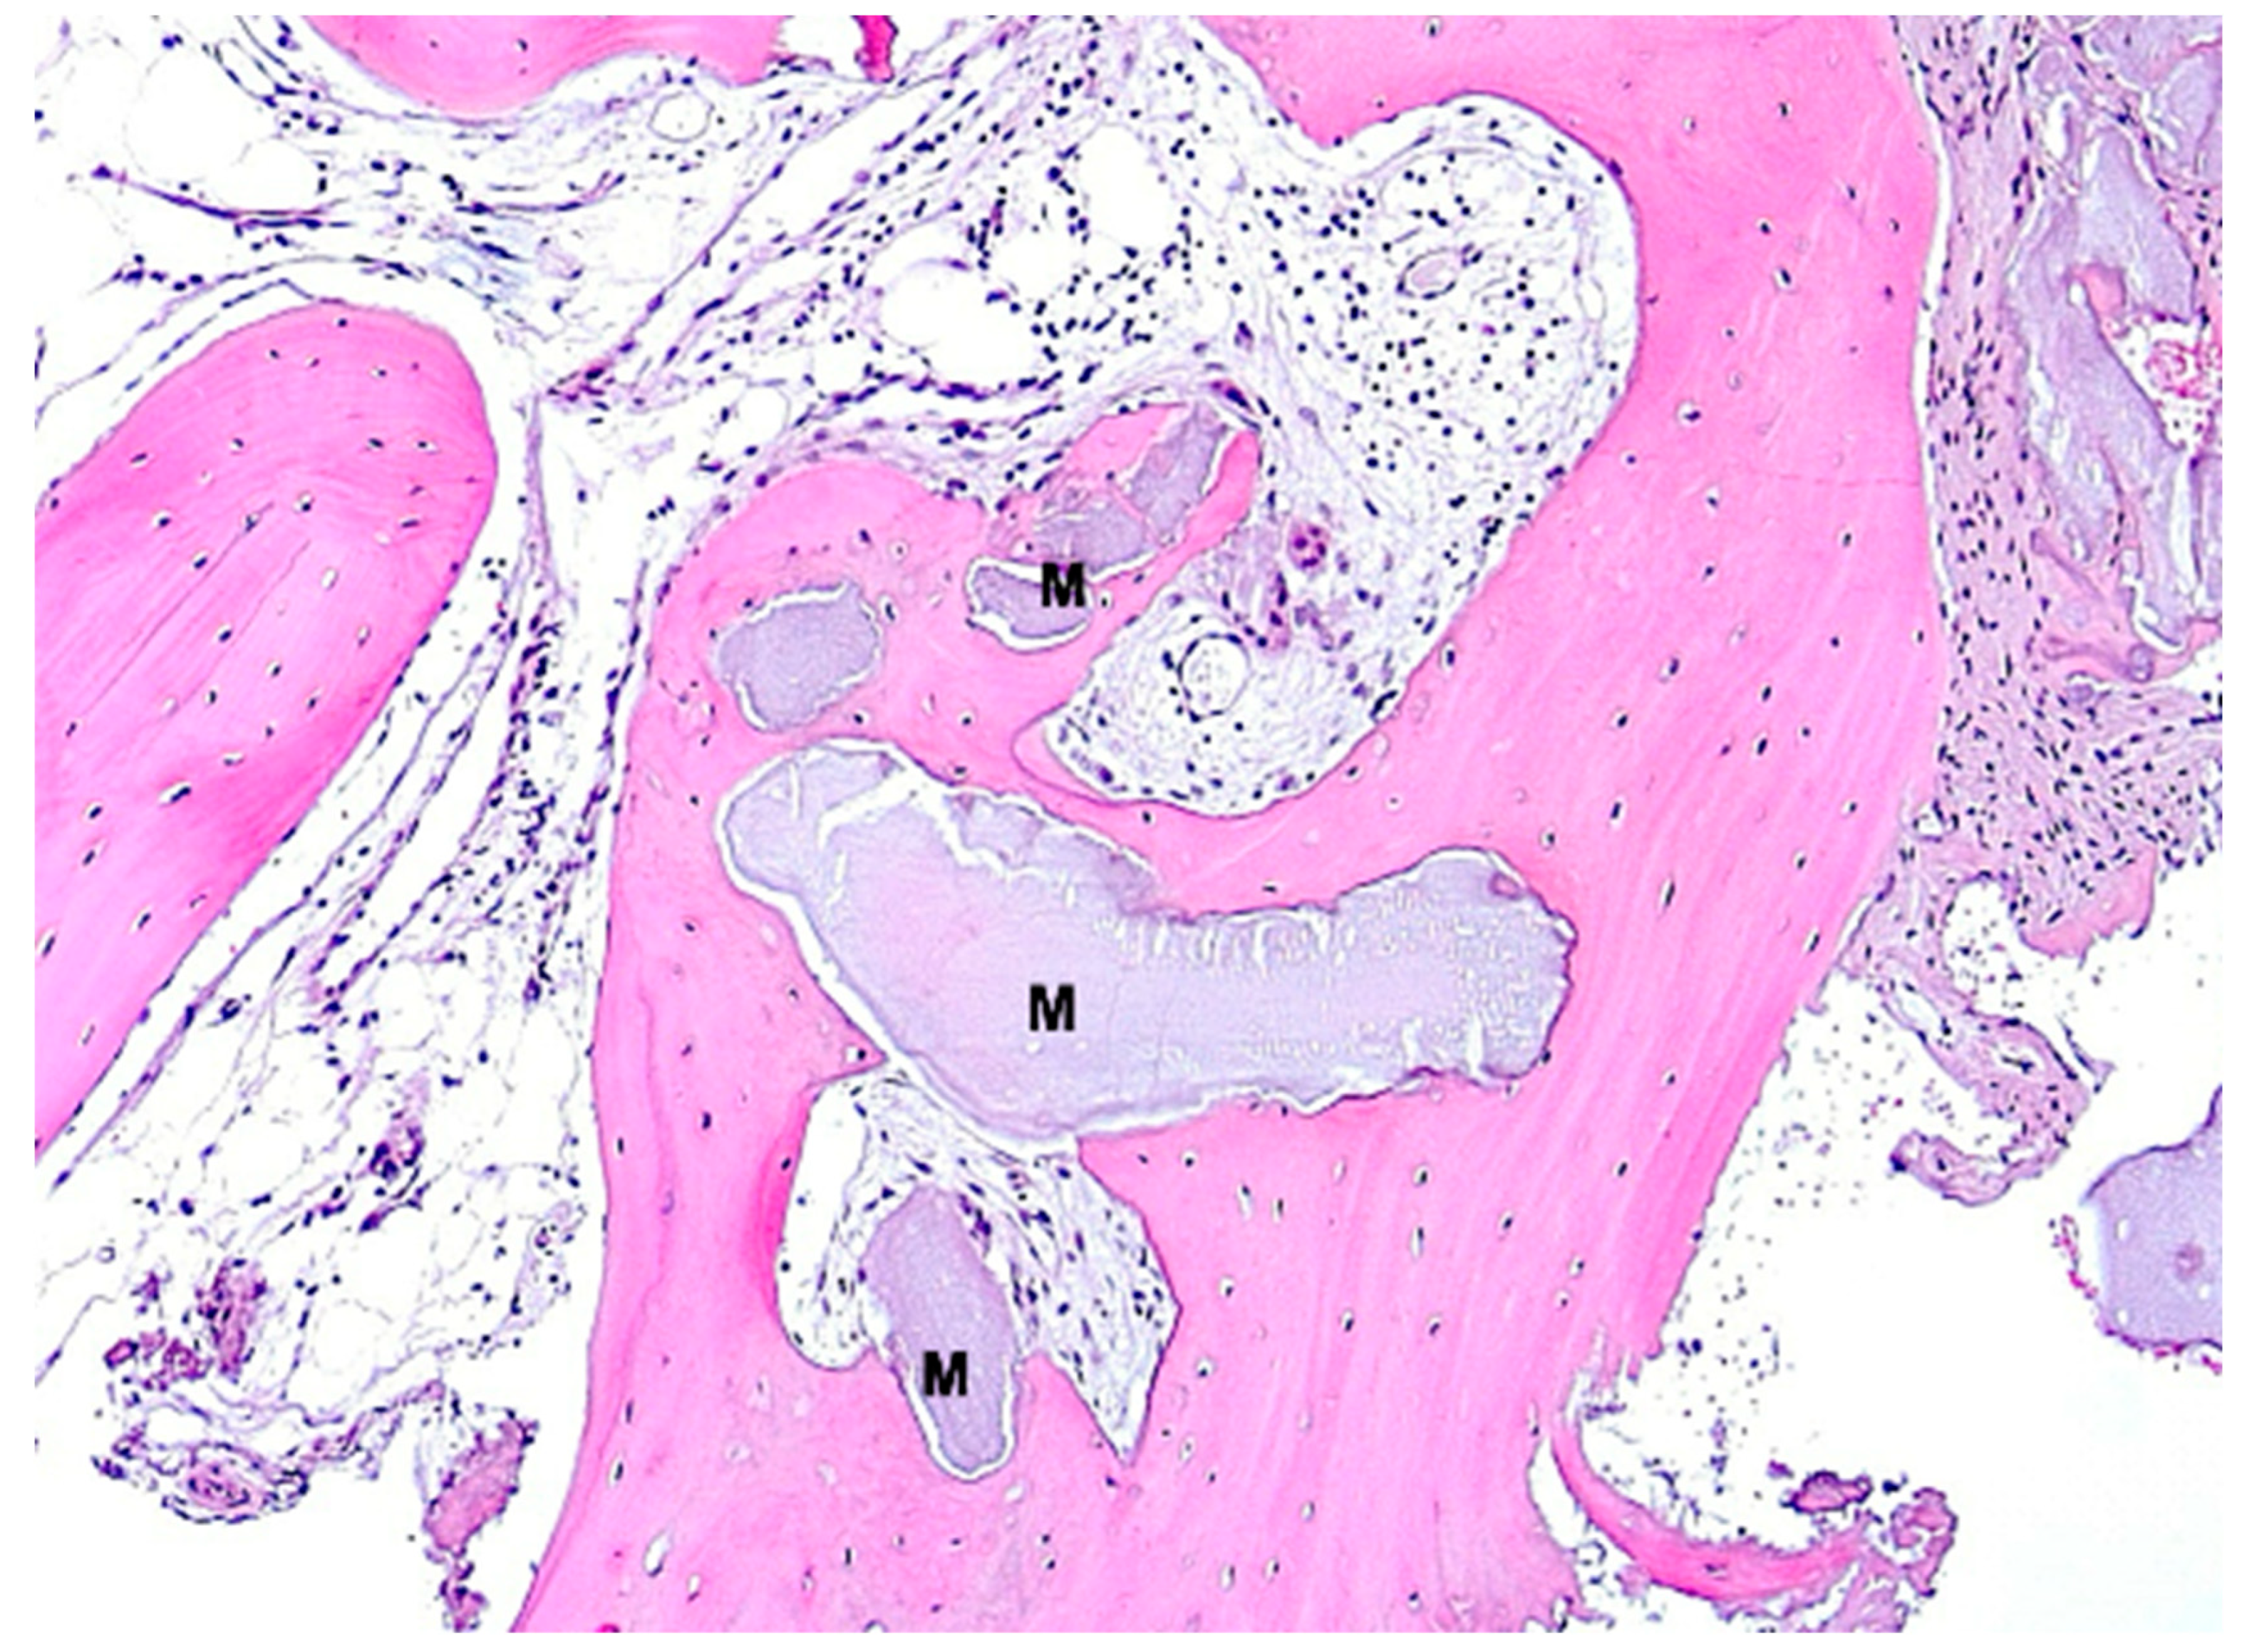

2.1. Histology

2.3. Histological Evaluation